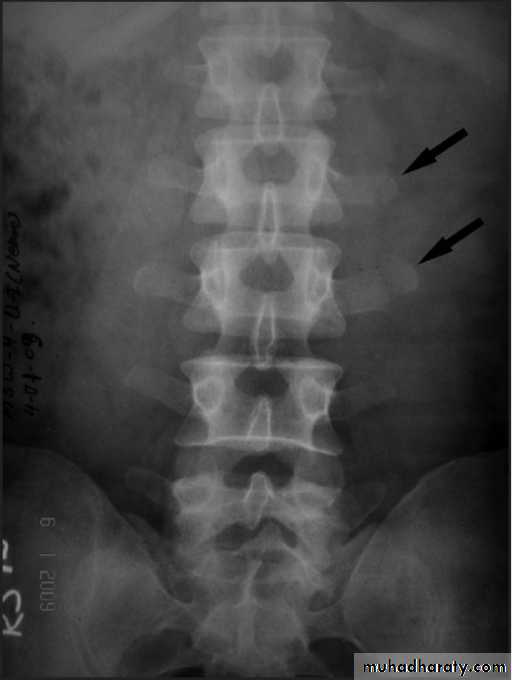

Dorsal and lumbar spine

Wedge compression fracture of a vertebral body.

Burst fracture of a vertebral body.

The thoracolumbar junction

one or more of the vertebral bodies collapses

anteriorly and becomes wedge-shaped, giving rise to a localized kyphosis.WEDGE COMPRESSION FRACTURE

Diagnosis .

obvious symptoms and signs pointingIn cases of major fracture there will be only between the T11 and L2